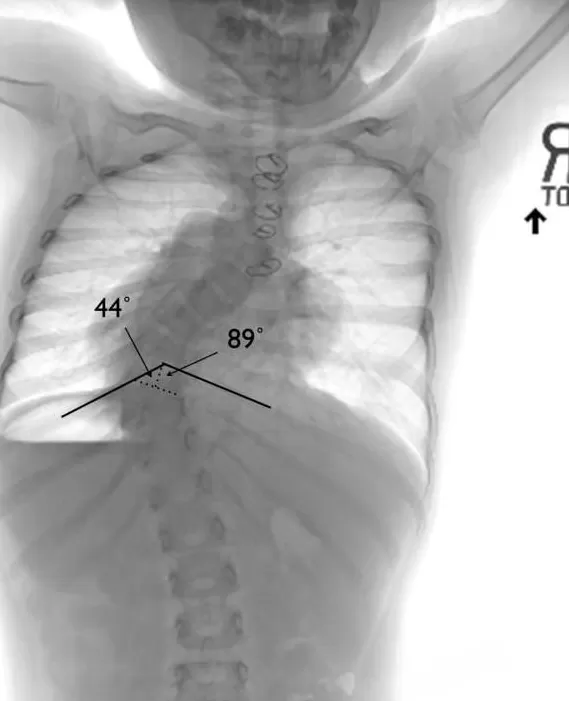

脊柱变形的影响远不止是外形上的改变。研究发现,如果在生长发育期出现明显的脊柱弯曲或畸形,会对胸腔和肺部的发育造成长期影响,容易引发 " 胸廓功能不足 ",从而导致呼吸困难或肺功能下降 [ 8 ] 。此外,脊柱畸形还会影响身高的正常增长,出现身材矮小或生长受限的情况 [ 9 ] 。

x 光片显示,患者由于脊柱变形,对肺部造成了压迫 / [ 8 ]